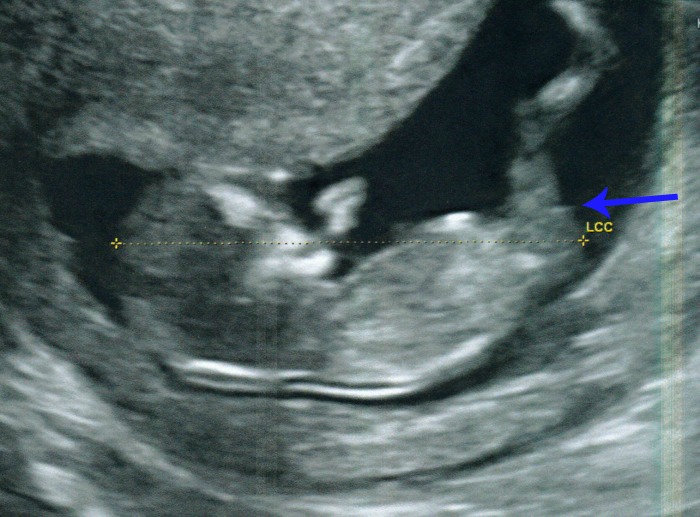

- Several times I saw a clear, long white nub... it was very straight and seemed longer than any of the other nub pictures on here. Not sure what long nub means?

- Numerous times I saw, in profile view, what looked like two white parallel lines. Both lines were shorter than the nub mentioned above but in the same place.

Unfortunately I dont have a clear picture of them but in the following picture you can see them but a bit fuzzy;

Here is another although this looks a little like 3 lines!

I am fairly sure that potty shots dont mean anything but here is the one we have anyway.... they were not checking sex here but measuring leg bone. Part of me thinks there is nothing there and when I look again it looks like a little turtle - am I going mad?!